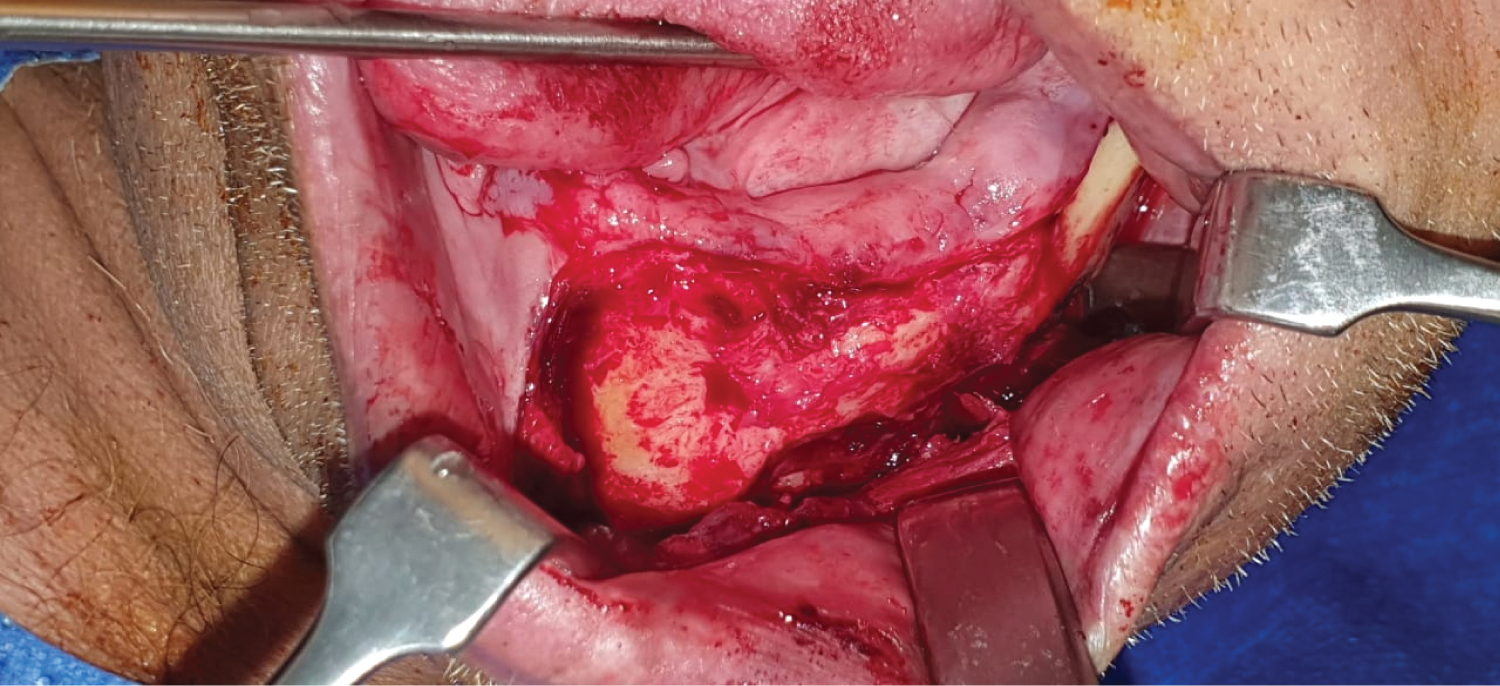

The remaining maxillary teeth extractions were performed in two surgical stages using atraumatic technique and socket filling with Advanced Platelet Rich Fibrin (A-PRF) plugs due to decreased local trauma in the affected area. Once elective surgical procedures were allowed during the pandemic period, we started with injections of liquid fibrin-rich plasma before lifting the intraoral mucoperiosteal flap to expose the affected site on the left mandible. Then, a surgical cleaning was performed to remove basilar bone sequestration, necrotic tissue, washing with injectable Clindamycin directly into the affected site, filling with A-PRF membranes [6] and fistulectomy. Notably, during intraoral exposure of the mandibular alveolar ridge, the presence of a fibrous callus was observed on the affected area without mobility in the margins, for which it was decided intraoperatively not to stabilize the bone fragments (Figure 2).

Figure 2: Intraoperative view showing fibrous callus formation in a site previously affected by ORN. View Figure 2